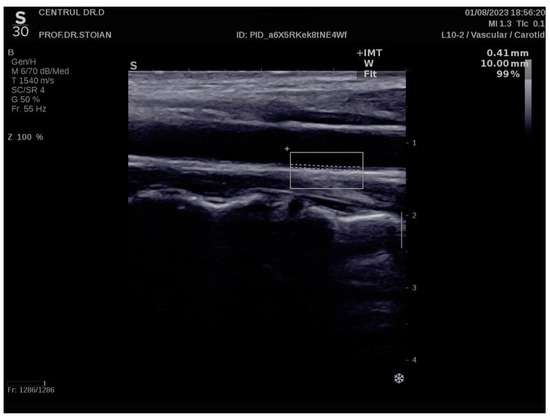

Figure 1 illustrates an example of CIMT evaluation for the left carotid artery obtained using this method in a normoweight subject, whose CIMT value falls within optimal limits. In contrast, Figure 2 depicts an elevated left CIMT value of 1 mm, observed in a patient with grade II obesity. It is important to note that personal data of the evaluated subjects are not displayed to ensure confidentiality.

Figure 1.

Example of a normal left CIMT measurement in a normoweight patient using the Aixplorer MACH 30 ultrasound system.

The Aixplorer MACH 30 ultrasound system (SuperSonic Imagine, Aix-en-Provence, France) was used to conduct an ultrasonographic assessment of carotid intima-media thickness. A certified and highly experienced sonographer conducted carotid ultrasonography on each participant included in this study. The procedure involved carefully positioning each subject to ensure optimal visualization of the carotid artery and applying a conductive gel to facilitate sound wave transmission. The sonographer then meticulously scanned the carotid arteries, using appropriate transducer settings based on individual anatomical characteristics, such as neck structure and adipose tissue distribution: SL 18-5 (5–18 MHz) or SL 10-2 (2–10 MHz). The CIMT values were automatically computed by the advanced software embedded within the ultrasound system (SuperSonic Imagine 3.0, Aix-en-Provence, France). This software analyzes the ultrasound images in real-time, providing precise measurements of the intima-media thickness without requiring manual calculation, ensuring both accuracy and efficiency in the evaluation process. The ultrasound images were captured during the end-diastolic phase, identified by the occurrence of the R wave on the electrocardiogram, ensuring consistency in arterial relaxation and minimizing variability in measurements [66]. For each participant, six separate CIMT measurements were taken, with three measurements performed on both the left and right carotid arteries. The measurements were carefully averaged to produce a mean CIMT value, which was subsequently used for analysis in this study. This approach helped to enhance the precision and reliability of the data by accounting for natural variations in arterial thickness across different locations and ensuring that the final CIMT value represented an accurate reflection of each patient’s vascular status. To obtain optimal visualization of the right and left common carotid arteries, the subject is positioned in a supine position and instructed to extend their neck backward as far as comfortably possible, enhancing exposure of the cervical region. Additionally, the examiner carefully chooses the most suitable ultrasound transducer, ensuring that the correct frequency range is used to maximize image clarity and resolution for accurate assessment of the CIMT. The scanning procedure begins with a transverse approach, starting at the clavicle and moving upward along the neck to identify the carotid bulb and the bifurcation of the common carotid artery into the internal and external carotid arteries. Once the carotid bulb is located, the examiner transitions to longitudinal scanning, allowing for a detailed assessment of the arterial walls and a more precise measurement of the CIMT along the length of the artery. This systematic approach ensures thorough visualization of both the structure and flow characteristics within the carotid arteries. In this section, the carotid bulb is visualized on the left side of the ultrasound screen. Measurements are taken from the posterior wall of the carotid artery, specifically 1 to 2 cm distal to the carotid bulb. This location is chosen to avoid the geometrical irregularities of the bulb itself and to obtain accurate and consistent CIMT values from a more uniform segment of the arterial wall [67]. At end-diastole, the image is frozen, and the software automatically measures the CIMT in the examiner’s selected region of interest, ensuring consistency and precision [68,69].